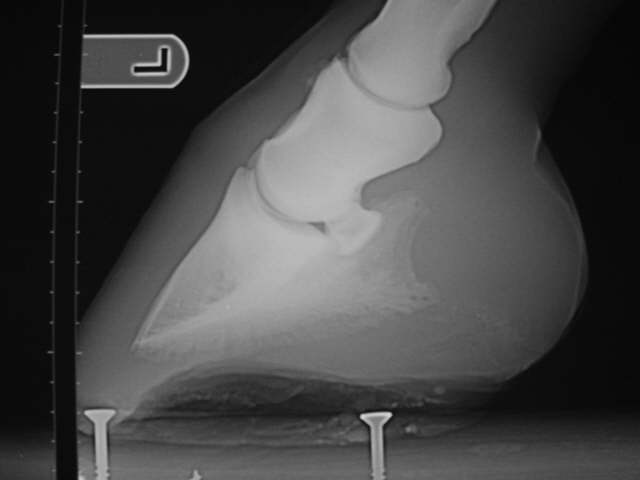

Enger Huf

Das Röntgenbild dazu.